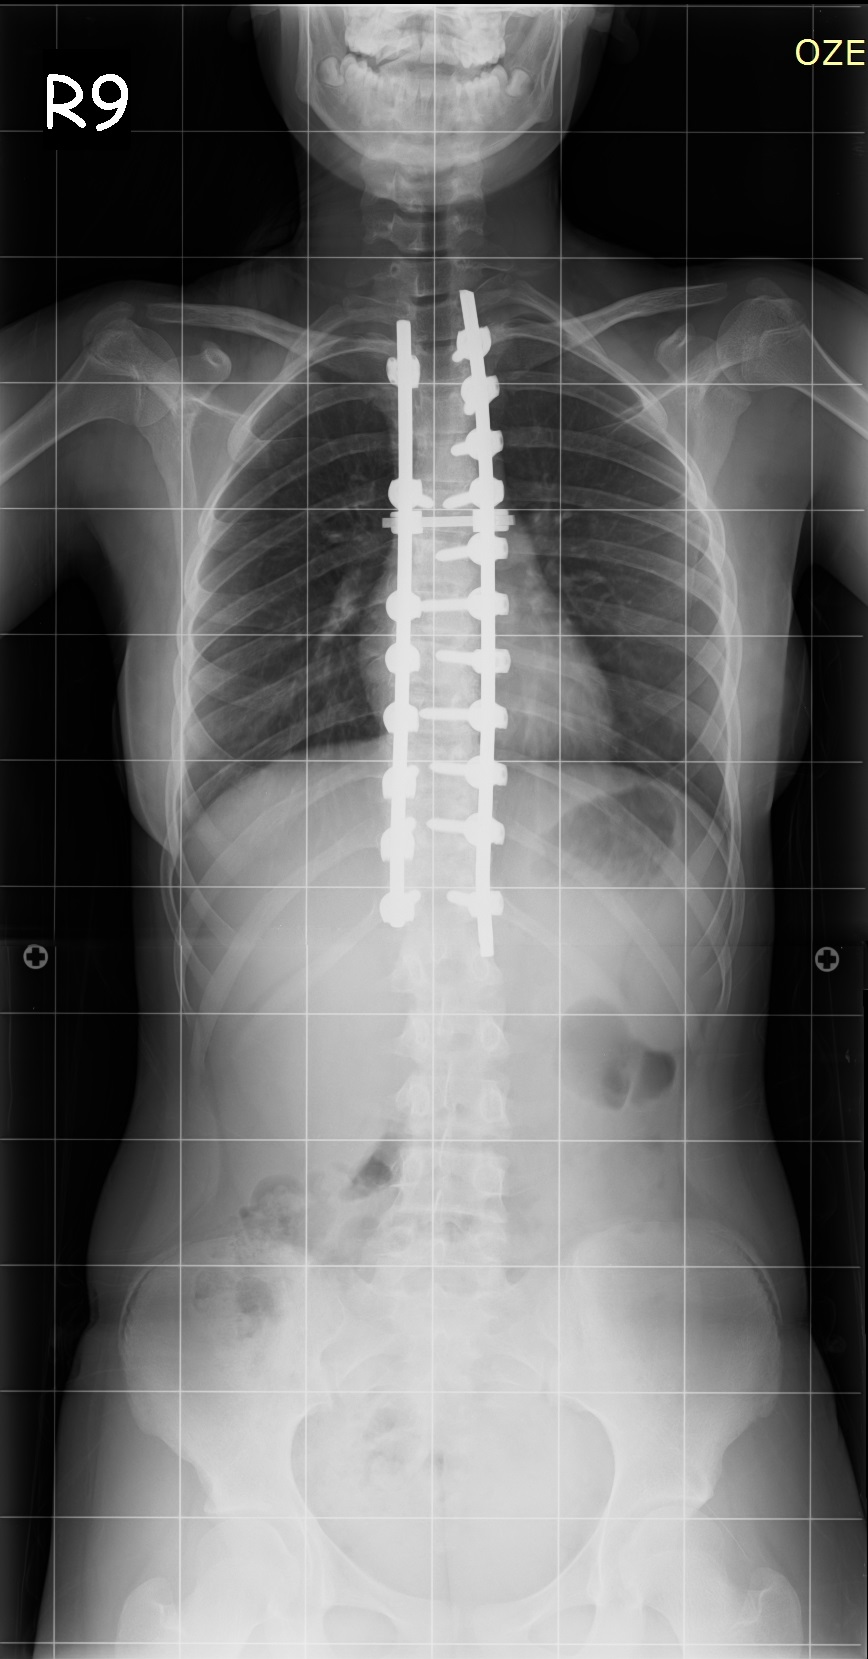

16 Yaşında Kadın Hasta

Ameliyat Öncesi

Ameliyat Sonrası